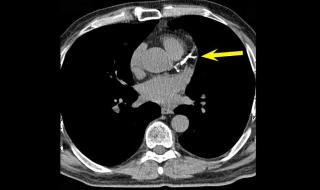

وأضاف النمر، عبر منصة (إكس)، أن التدخين السلبي باستنشاق دخان الآخرين؛ يرفع خطر الإصابة بأمراض القلب بنسبة 25% مقارنة بغير المدخنين.

وتابع النمر، أن المدخن النشط ترتفع لديه خطورة امراض القلب بمقدار ضعفي خظورة المدخن السلبي؛ لذلك فالجلوس بجانب المدخن ليس آمناً كما يظن البعض.